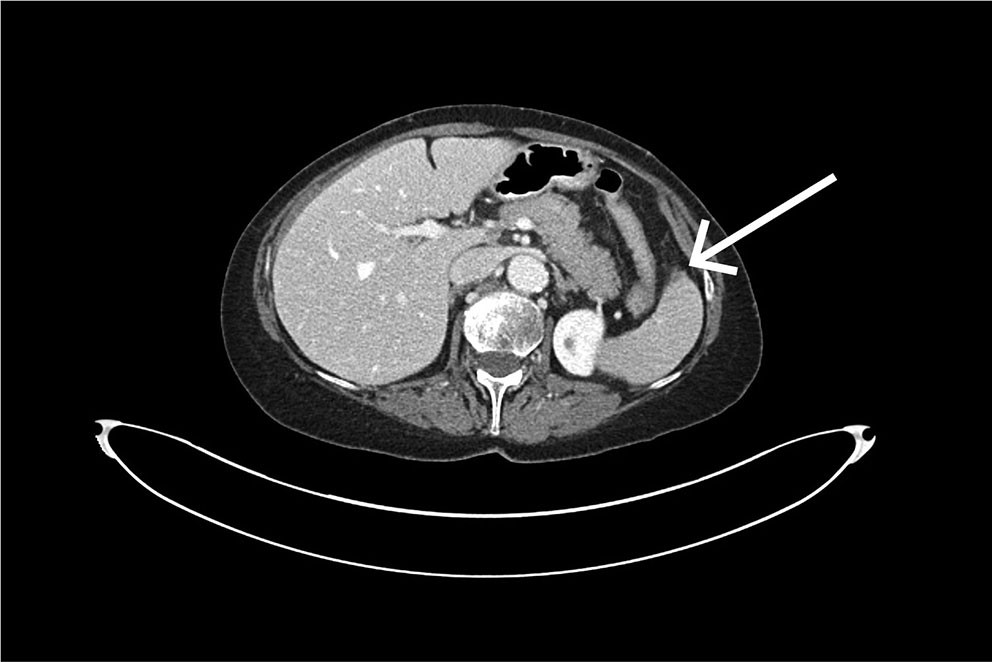

Det ble tatt CT av abdomen og bekken med intravenøs kontrast i portovenøs fase som øyeblikkelig hjelp. Undersøkelsen viste et stort, subkapsulært milthematom og en liten miltlaserasjon (figur 1). Man konkluderte med sannsynlig kapselruptur med blødning ut i fri bukhule, med væskeansamling perihepatisk, parakolisk og i det lille bekkenet. Ved regranskning av CT-undersøkelsen tatt like etter koloskopi kan man ved nærmere ettersyn se en liten subkapsulær miltlaserasjon i området for feste av ligamentum splenocolicum (figur 2).